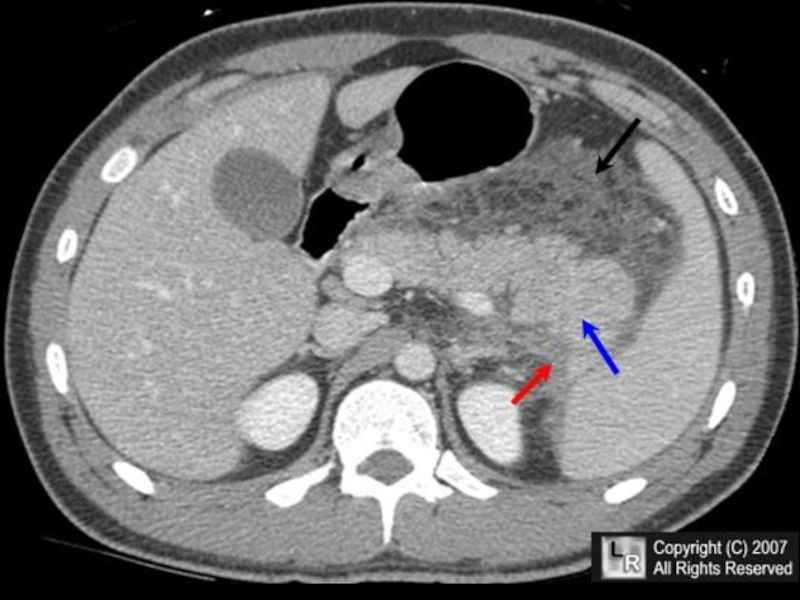

- Computed Tomography (CT) scan: Provides detailed cross-sectional images of the abdomen, allowing for precise measurements of spleen size.

Evaluating Blood Flow

Color Doppler and power Doppler ultrasound techniques allow for assessment of blood flow within the spleen and its surrounding vessels. This information can be valuable in detecting:

- Portal hypertension

- Splenic vein thrombosis

- Abnormal vascular patterns associated with certain tumors